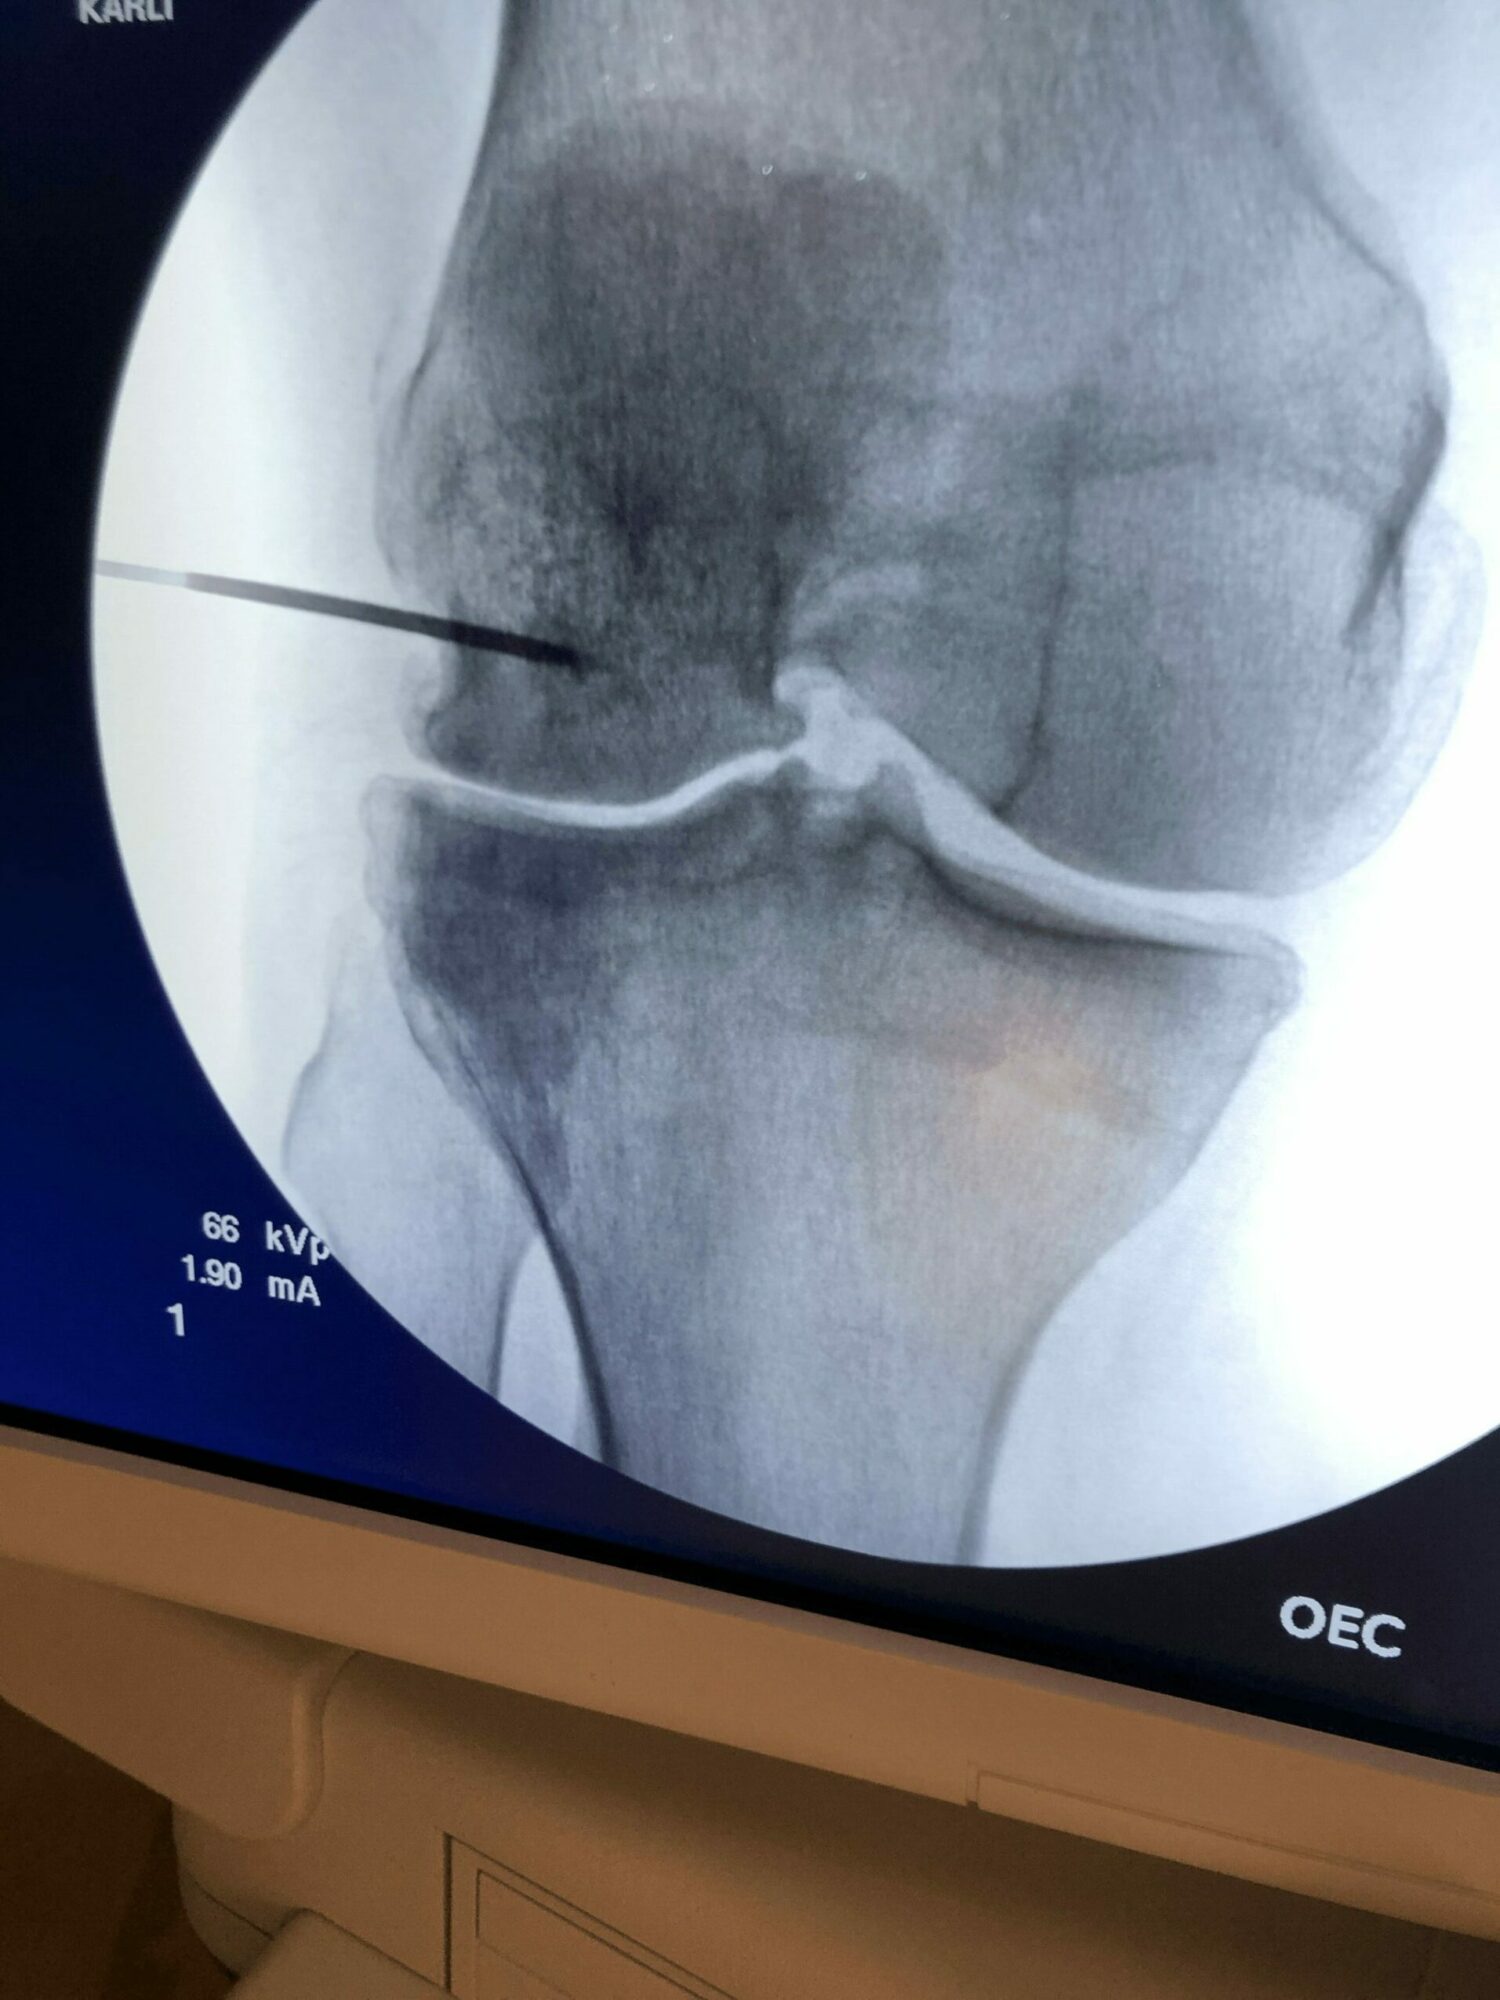

Platelet Rich Plasma (or PRP) was very new to the scene. An experimental treatment which concentrated platelets from a patient’s own the blood, injected to treat common Orthopedic problems like arthritis. Platelets coordinate healing in our body. The problems I had been trained to treat with medications, steroid injections and physical therapy. were frustrating me for years, reducing symptoms short term at best, but not solving the problems. I could park steroid anywhere in the body that I wanted with extreme precision using Xray or ultrasound guidance, only to see the patient back a few months later with the same pain. The common thread for most orthopedic problems was that the tissues all had a lousy blood supply, so they had little to no capacity to heal themselves and that’s why they become chronic sources of pain with age and after injury.

PRP made more sense to me. Delivering the body’s healing tools to places that they couldn’t get to normally, in an effort to stimulate healing, reduce inflammation and pain naturally, and keep it that way was logical. I had treated my own knee tendon with PRP – suffering for many years with intense pain – right at the bottom of my kneecap. After trial and error – PRP was the only thing that allowed me to solve the problem.